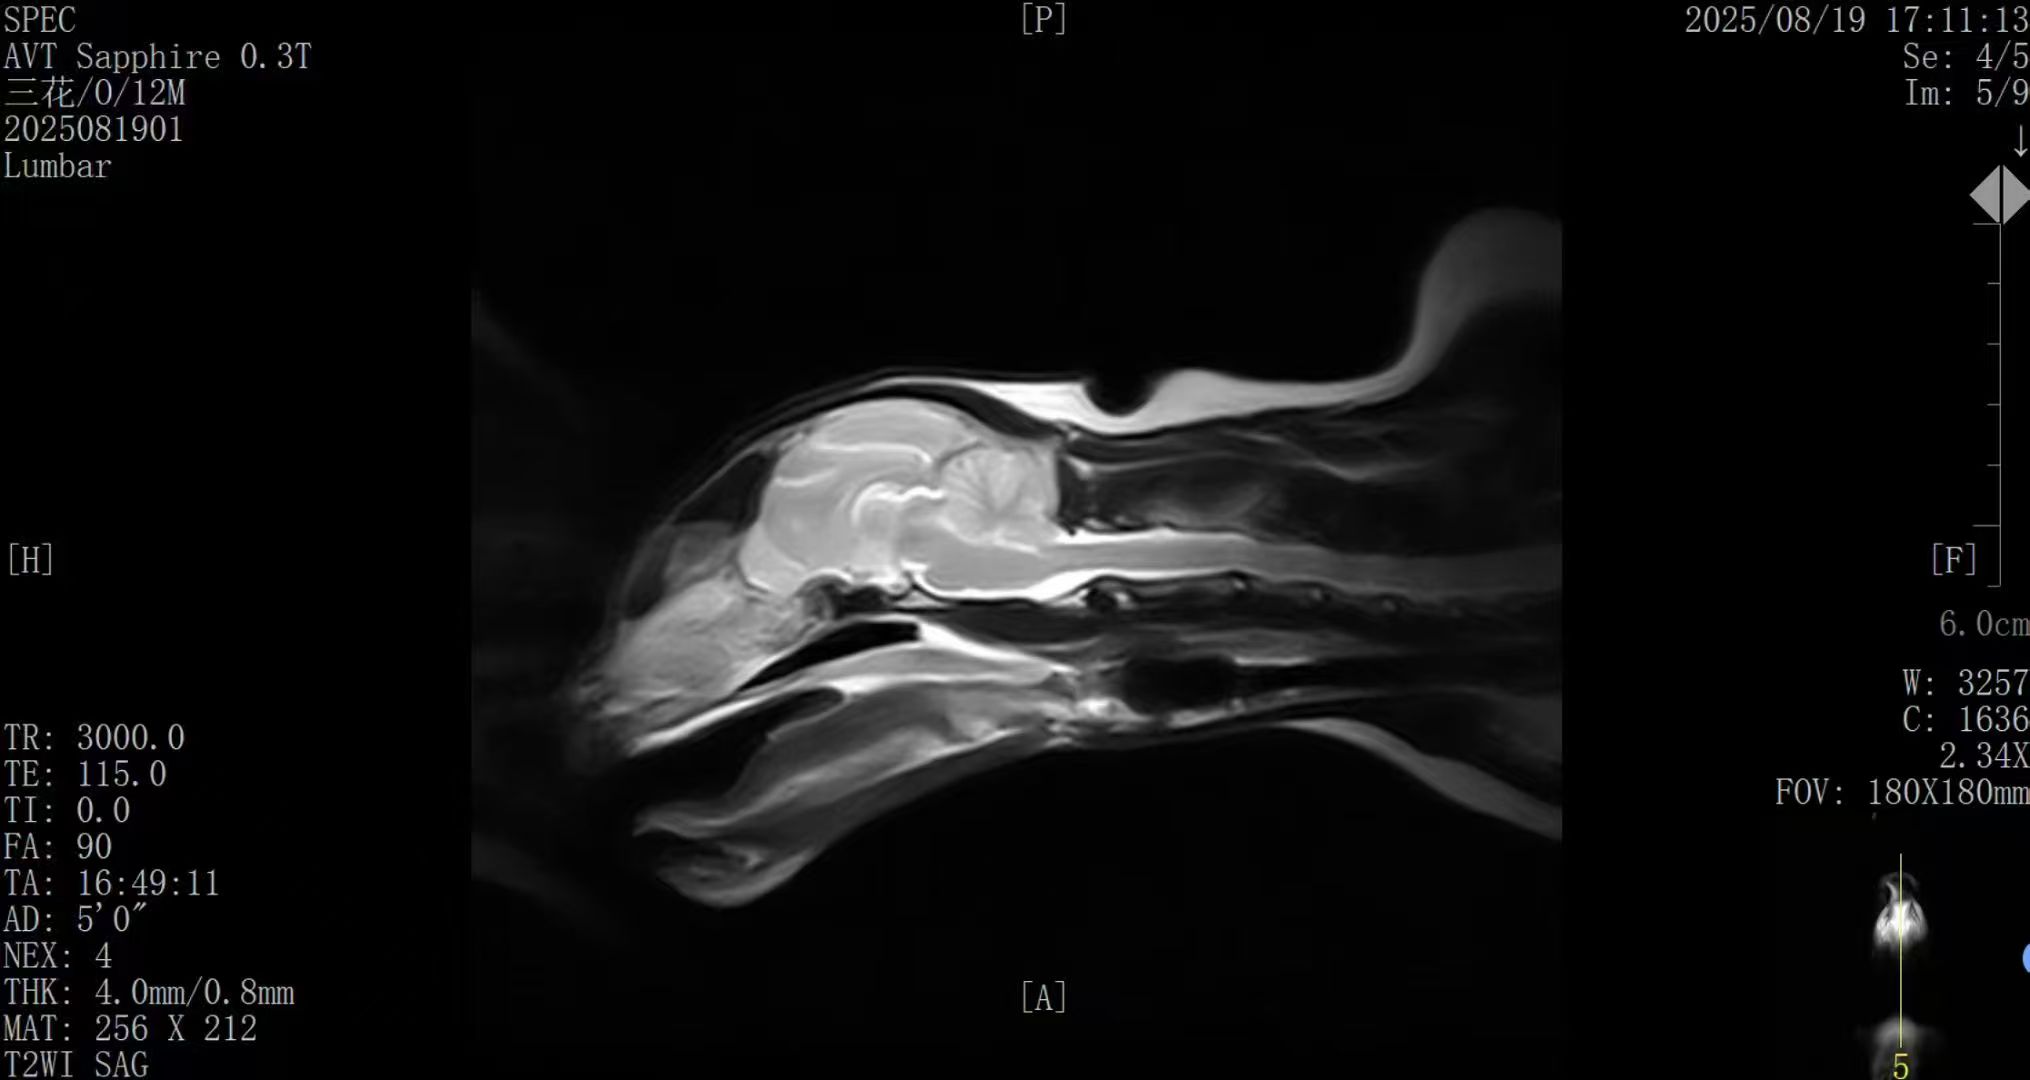

本次展出的AVT plus 0.3T轻量型MRI,是斯派克针对宠物医疗市场推出的高性能、低门槛成像解决方案。该设备采用永磁自屏蔽一体化设计,重量仅3吨,无需额外屏蔽间与设备间,极大节约医院空间,且无需楼层加固,安装灵活便捷。设备搭载AI智能优化成像系统,图像质量持续优化,在软组织对比度、多方位断层成像等方面表现优异,完全满足宠物临床诊断需求。

脑花部位清楚可见,绝对是宠物医院极具性价比的选择。